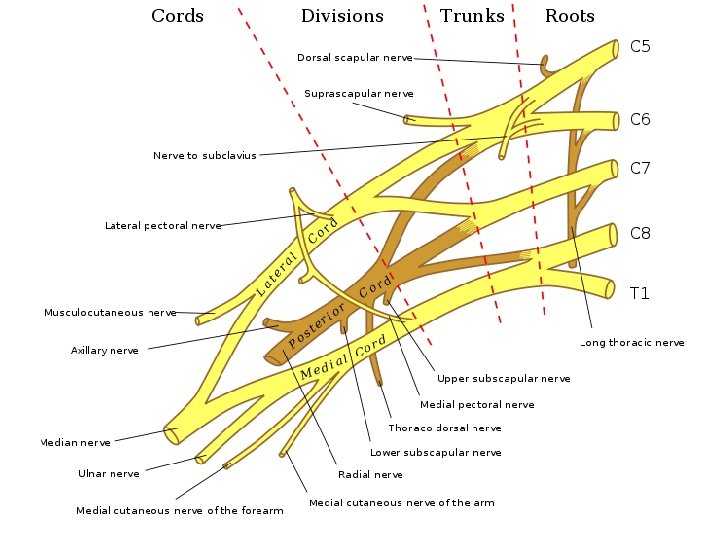

Pars infraclavicularis plexus brachialis - fasciculus medialis - fasciculus lateralis - fasciculus posterior

PARS SUPRACLAVICULARIS Truncus superior – C 5 -C 6 (C 4) Truncus medius – C 7 Truncus inferior - C 8 -T 1 (T 2) Prefixed type: C 4 – C 8 Postfixed type: C 6 – T 2

PARS SUPRACLAVICULARIS N. dorsalis scapulae (C 4, C 5) - mm. rhomboidei - m. levator scapulae N. thoracicus longus (C 5, C 6, C 7) - m. serratus ant. N. subclavius (C 5, C 6) - m. subclavius - art. sternoclavicularis N. suprascapularis (C 5, C 6) Rr. musculares - mm. scaleni - m. longus colli

N. pectoralis lateralis (C 5, C 6, C 7) - mm. pectorales N. pectoralis medialis (C 8, T 1) - mm. pectorales N. subscapularis sup. (C 5) - m. subscapularis N. subscapularis inf. (C 6) - m. subscapularis - m. teres major N. thoracodorsalis (C 6, C 7, C 8) - m. latissimus dorsi

PARS INFRACLAVICULARIS (terminal branches) Fasciculus posterior - n. axillaris - n. radialis Fasciculus lateralis - n. musculocutaneus - radix lateralis n. mediani Fasciculus medialis - radix medialis n. mediani - n. ulnaris - n. cutaneus antebrachii med. - n. cutaneus brachii medialis